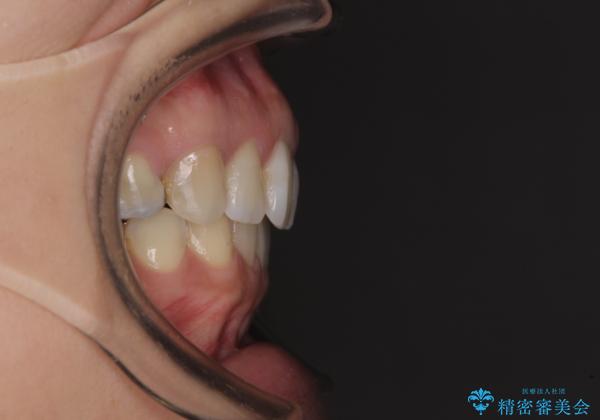

- 上の前歯の捻じれと突出感を気にして来院された患者様です。

目立たない装置を希望とのことで、上顎左右第一小臼歯を抜歯し、インビザラインにて矯正治療を行うこととしました。